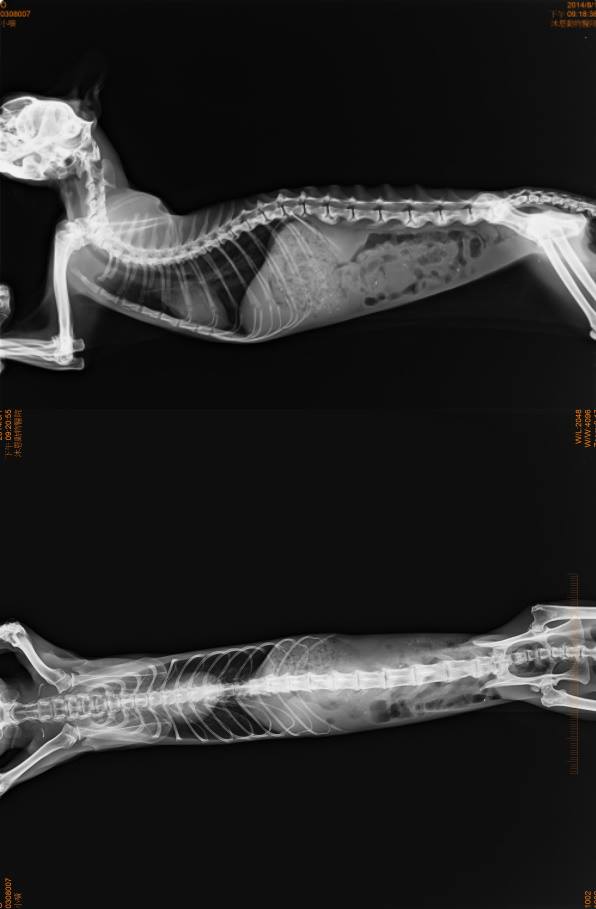

- 編號: 4807

主題: 生病被丟棄的摺耳貓 申請者姓名: 陳曉霏 花色: 申請日期: 2014-08-14 19:48:36 申請者部落格: 申請者臉書網址: 所在縣市/合作醫院: 台北市/沐恩動物醫院 治療費用: 10000元 需求人數: 11人 已結案 (2014-09-04 10:06:38) 報名人員: Niki、Patrick x2(已付款)、Limon(已付款)、Ski、Sku、Sku(已付款)、beforn(已付款)、jiun(已付款)、liyinliao x2(已付款)、徐二花(已付款)、拐拐、么么的媽咪(已付款)、JasmineC(已付款)、 候補人員: 西瓜巧比、austin0529、 動物病情說明: 噴噴 是他現在的名子

不料 一摸身體 居然發現他已呈現脫水狀態

牙齦比雪還白

在第一間醫院 醫生建議需要馬上住院上點滴

血檢出來後 是呈現爆肝 嚴重貧血的狀態

緊急轉院到協會配合的重症醫院

經過多日的調養

所有指數都漸漸好轉

相信應該是被棄養前 就已經長期營養不良了

目前孩子安置在協會努力養胖 養身體當中

以後他在也不會有機會被棄養了